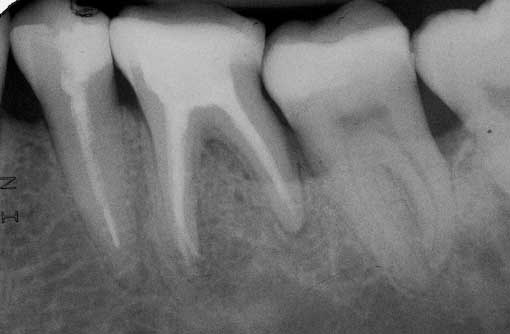

Veröffentlicht 2. Dezember 2008 am 510 × 334 in 3 mesiale Kanalausgänge (2)

Zahn 36 WF – Kontrolle orthograd 11 Monate post WF